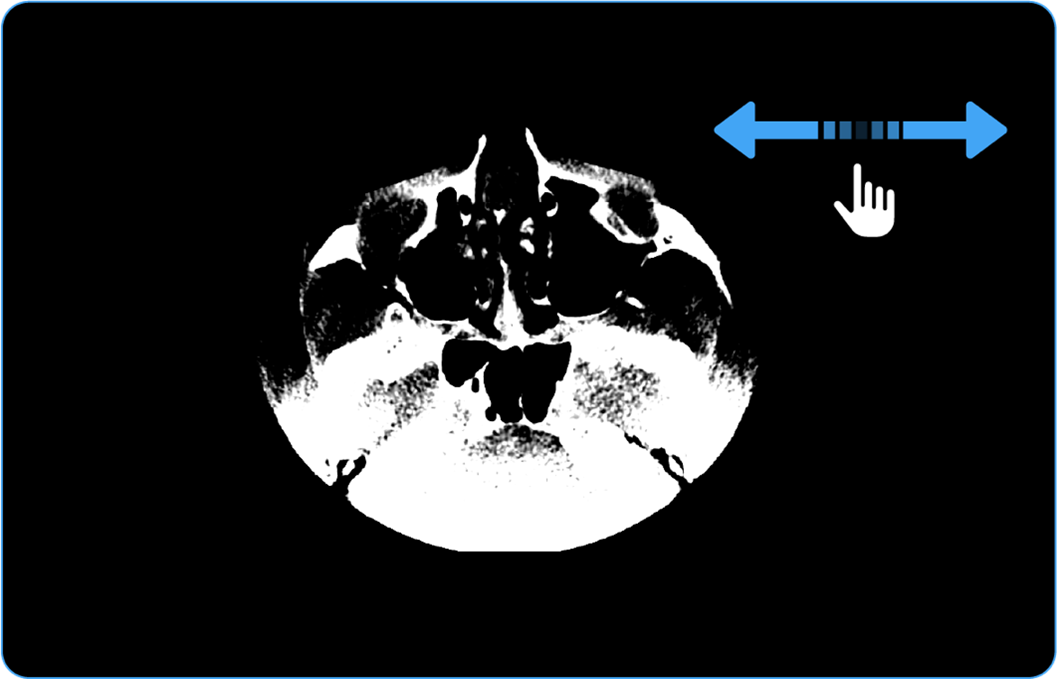

Viewing Images in Completed Appointments

• Go to Completed Appointments and select the desired study.

• Tap View Results to open the Study Information Page.

vai

• Locate and tap View Images to access the available images.

• Use finger touch to PAN the images.

• Pinch in/out to zoom in or out.

• Scroll sideways to navigate through other images in the series.